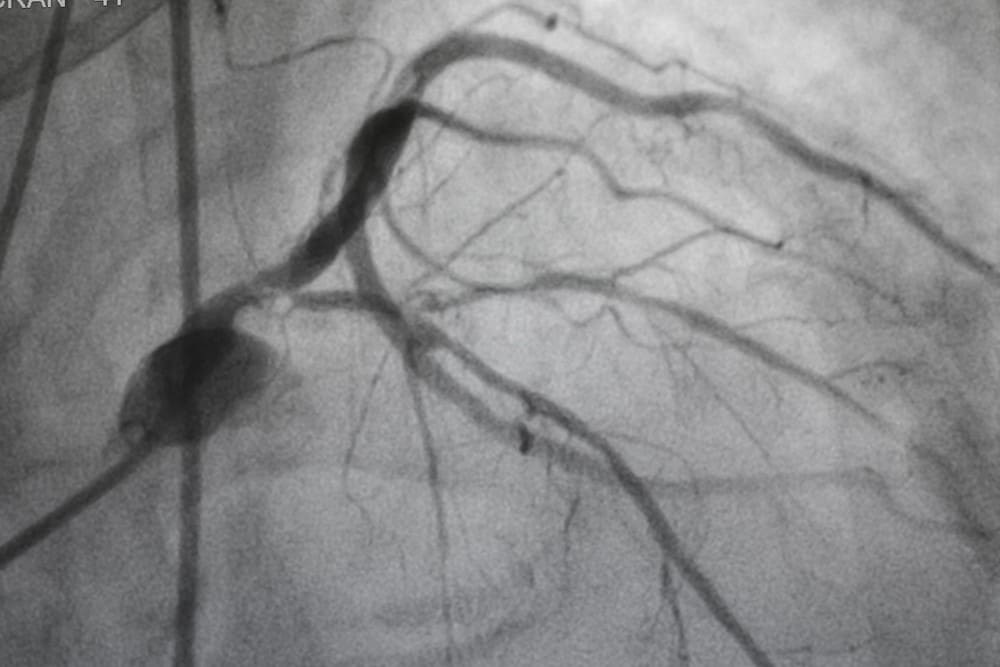

Mahfud: Saat itu pagi hari dan saya beristirahat. Di siang harinya, saya mengalami nyeri yang sama dan merasa gelisah, serta merasakan ada yang tidak tepat pada dada saya. Akhirnya saya meminta Paman saya mendampingi untuk melakukan pengecekan ke salah satu rumah sakit di pusat kota Semarang. Saat itu juga, saya bertemu dengan dokter jantung. Dan hal pertama adalah saya menyadari bahwa tekanan darah saya cukup tinggi di atas 155! Dokter lalu meminta saya mengecek kadar kolesterol saya lewat test darah. Hasil lab menyimpulkan kadar LDL saya sudah cukup tinggi di angka 170mg/dL. Dari situ, dokter mendiagnosa adanya penyumbatan awal pada pembuluh darah jantung saya, merujuk dari hasil darah dan keluhan yang saya rasakan. Selanjutnya dokter menyarankan saya melakukan test angiography untuk mengecek ada/tidaknya sumbatan pada pembuluh darah jantung saya. Namun karena saat itu disarankan menginap, saya memilih untuk pulang dahulu dan berniat melanjutkan pengecekan di keesokan hari.